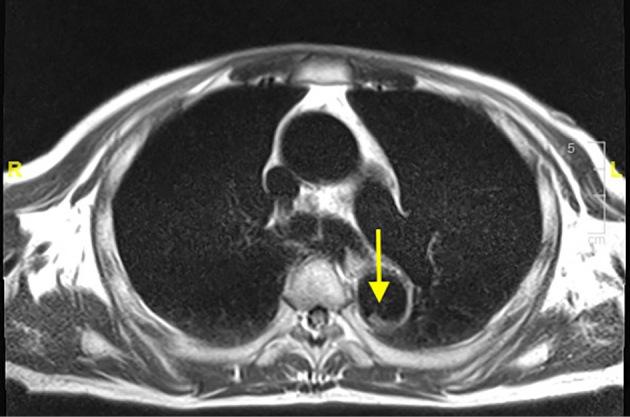

Spontaneous Cholesterol Crystal Embolism and Aortic Plaques.

Intern Med. 2021 Jun 15;60(12):1981-1982. doi: 10.2169/internalmedicine.6511-20. Epub 2021 Jan 15.

DOI:10.2169/internalmedicine.6511-20

PMID:33456045